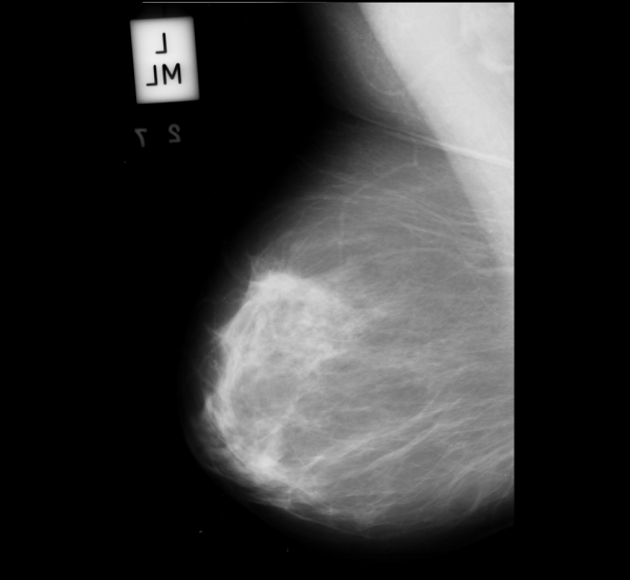

Neural networks require a large number of images as input for the training purposes. Because of limited resources of large dataset availability, the dataset used for this research is mini MIAS dataset [10]. It comprises of total 322 images which are further divided into a number of classes. Original size of each image in the dataset is 10241024. Sample images are shown in Figure 1.

3 Dataset